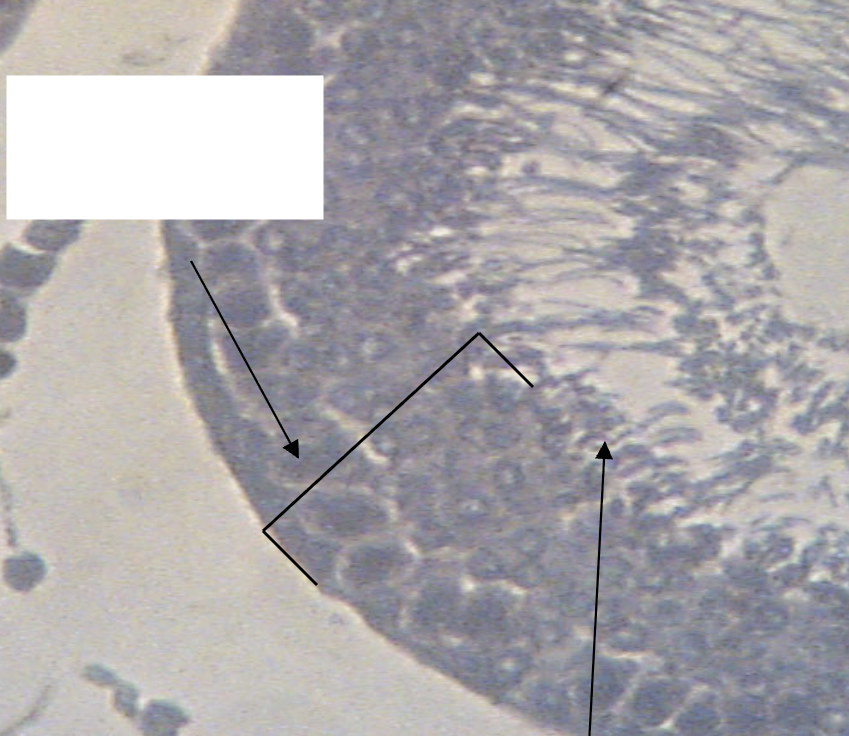

What structures are being indicated by the leftmost arrow?

Sertoli cells

What structures are being indicated by the rightmost arrow?

Spermatogonia

What structures are being indicated by the above arrow?

Seminiferous epithelium

What structures are being indicated by the lower arrow?

Spermatids